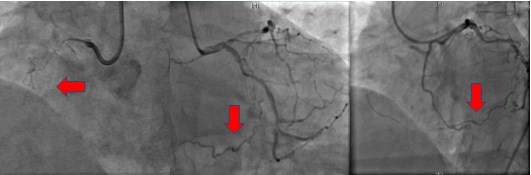

今天这位患者为一名70岁的老年女性,在1年前因骨折于外院住院期间突发心绞痛,行冠状动脉造影提示右冠状动脉(Right Coronary Artery,RCA)近端完全闭塞,辗转多家医院行冠状动脉造影并尝试开通冠状动脉均失败,平素给予阿司匹林等药物维持治疗。此后患者反复受心绞痛的折磨,日常生活受到明显限制。1周来胸痛症状加重,患者常常于睡眠中被疼痛憋醒,无奈之下来到我院心脏内科门诊。经过仔细评估后,为了改善患者心绞痛的症状,预防随后可能发生的心肌梗死甚至心脏性猝死等严重并发症,心脏内科介入团队在著名冠脉介入治疗专家王伟民教授指导下,为患者再次行冠状动脉造影,结果显示右冠状动脉完全闭塞,而左侧的回旋支动脉为闭塞的右冠状动脉提供了一支良好的侧支循环,如图1所示。 (A) (B) (C)

图1 冠状动脉造影。A图, 右冠状动脉走形区域无造影剂充盈,提示血管完全闭塞;B图,左冠状动脉的回旋支为右心室提供侧支循环;C图,左侧冠状动脉提供的侧支循环闭塞的右冠状动脉远端连通。